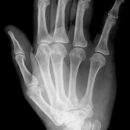

Hand a.p. (dorsovolar)

Lagerung

Patient sitzt seitlich am Tisch, der abgewinkelte Unterarm und die Handflächen liegen auf, Finger leicht gespreizt, evtl. Sandsack zur Fixierung auf den Unterarm legen.

Zentralstrahl

Auf Objekt- und Kassettenmitte.

Anmerkung

Übersichtsdarstellung des Skeletts bei Frakturen, Arthrosis und Deformierung der Gelenke, sowie chronischer Polyarthritis (Rheuma).

Qualitätskriterien

Vollständige Abbildung der ganzen Hand einschließlich aller Fingerendglieder und des Handgelenkes.